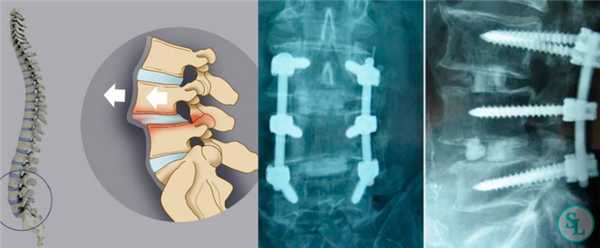

Жесткие стабилизирующие системы

Системы жесткой фиксации подразумевают установку в межпозвонковое пространство костного трансплантата (обычно взятого из подвздошной кости пациента) или специального искусственного кейджа с последующим монтажом на два и более соседних позвонка металлической конструкции. В результате они обездвиживаются и со временем сращиваются между собой, т. е. происходит спондилодез.

Жесткая стабилизация подразумевает использование техники транспедикулярной фиксации или транскутанной стабилизации. Они очень похожи между собой и отличаются одинаковой эффективностью, но последняя обладает лучшим косметическим эффектом, поскольку все манипуляции осуществляются через точечные проколы мягких тканей.

Суть метода состоит в применении специальных титановых винтов и пластин. Винты вкручиваются в точку пересечения поперечных отростков позвонка с суставными по обеим сторонам позвонка. Таким образом, фиксируется минимум 2 позвонка, хотя в ряде ситуаций требуется стабилизация значительного большего количества позвоночно-двигательных сегментов. Через шляпки винтов пропускают титановую пластину, обеспечивающую жесткость конструкции и распределение нагрузки на нее.

Стабилизационная система на рентгене.

В большинстве случаев проблемный сегмент стабилизируют с помощью металлоконструкций, чаще представленных транспедикулярными системами и пластинами с винтами из высокотехнологичных сплавов металла. В хирургии такая техника называется инструментацией позвоночника. Кроме металлоконструкций, для стабилизации также могут быть применены полимерные устройства, сделанные, например, из углеводородного волокна или резорбирующегося высокомолекулярного биополимера. К отдельной разновидности стабилизирующих вмешательств, которые не причисляют к инструментации, относят установку кейджей имплантатов межпозвоночных дисков.

Стабилизация поясничного отдела.

Транспедикулярная фиксация позвоночника

Транспедикулярная фиксация или ТПФ - операция, при которой позвонки фиксируются и стабилизируются при помощи специальных имплантов (транспедикулярных винтов). В каждом позвонке есть точка ввода винта, которую установил в 1985 году Рой Камилл — это точка пересечения поперечного отростка позвонка с верхнем суставным отростком. С помощью специальных инструментов в эту точку, вкручиваются винты определяя анатомически правильное расположение позвоночника, тем самым излечивая заболевание. Первые попытки установки имплантов были в 60-70 гг. прошлого века и с тех пор является «золотым стандартом» в лечения переломов и различных заболеваний позвоночника.

Нестабильность позвоночника считается одним из распространенных заболеваний и основным методом лечения является транспедикулярная фиксация подвижного сегмента, декомпрессивная ляминэктомия, дискэктомия с установкой между телами позвонков кейджа который фиксирует сегмент на 360 градусов (золотой стандарт). В подобных ситуациях метод обеспечивает надежный спондилодез у 80- 95% пациентов. ТПФ является одним из наиболее часто применяемых методов оперативного лечения заболеваний и травм в связи с тем, что современные хирурги стараются добиться спондилодеза на 360°. Достичь этого позволяет сочетание ТПФ с межтеловым спондилодезом, что обеспечивает высокую частоту костных сращений и отсутствие остаточной незначительной подвижности в передних отделах прооперированного сегмента. Поэтому при успешном завершении операции и правильном восстановлении пациенты гарантировано избавляются от болевого синдрома.